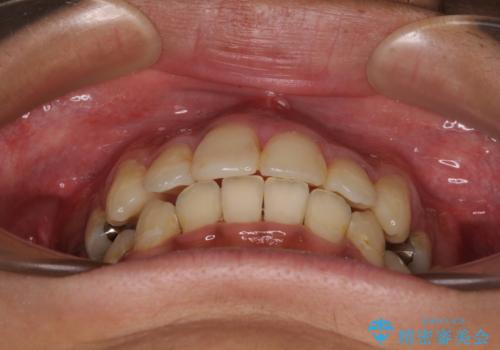

八重歯と開咬 ワイヤー装置での抜歯矯正

舌の突出癖により開咬となっていたため、突出癖改善のためのトレーニングをしっかりと行っていただき、予定の期間で無事に治療を終えることができました。